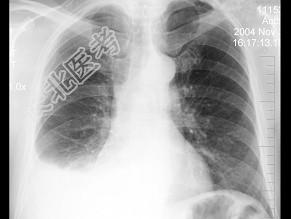

- 单项选择题男,66岁, 近1月来感胸闷,有时低热, 胸片如图,最可能的诊断为 ( )

A、化脓性胸膜炎

B、结核性胸膜炎

C、右下肺炎症

D、右下肺不张

E、右侧胸腔积液